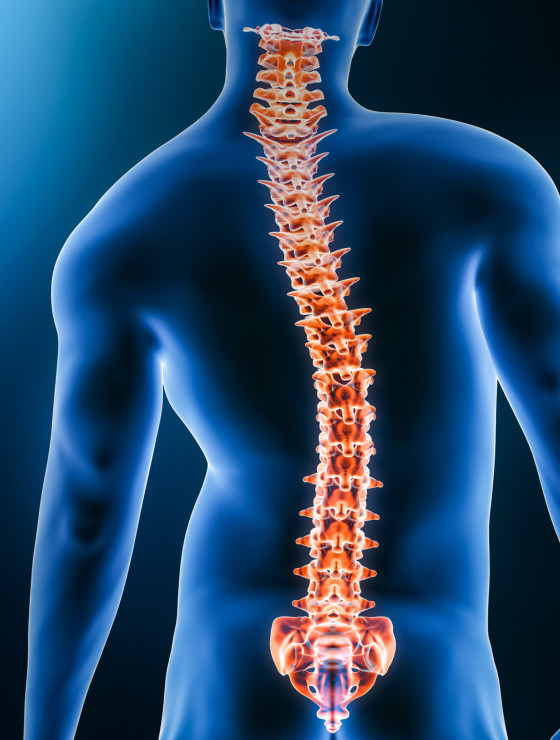

Cirurgião especializado no diagnóstico, tratamento e correção de problemas da coluna vertebral.

Dr. Fernando Soccol é médico ortopedista referência em cirurgia da coluna vertebral, com mais de uma década de experiência, expoente na área de cirurgia minimamente invasiva e cirurgia endoscópica da coluna.

Cirurgias na coluna são seguras e previsíveis. Ao longo das últimas décadas observou-se refinamento das técnicas operatórias e dos equipamentos de projeção de imagens, como microscópios e vídeo-endoscópios. Hoje é possível “navegar” em cirurgias guiadas por tomografia tridimensional, além de monitorar a atividade neurológica do paciente em tempo real.